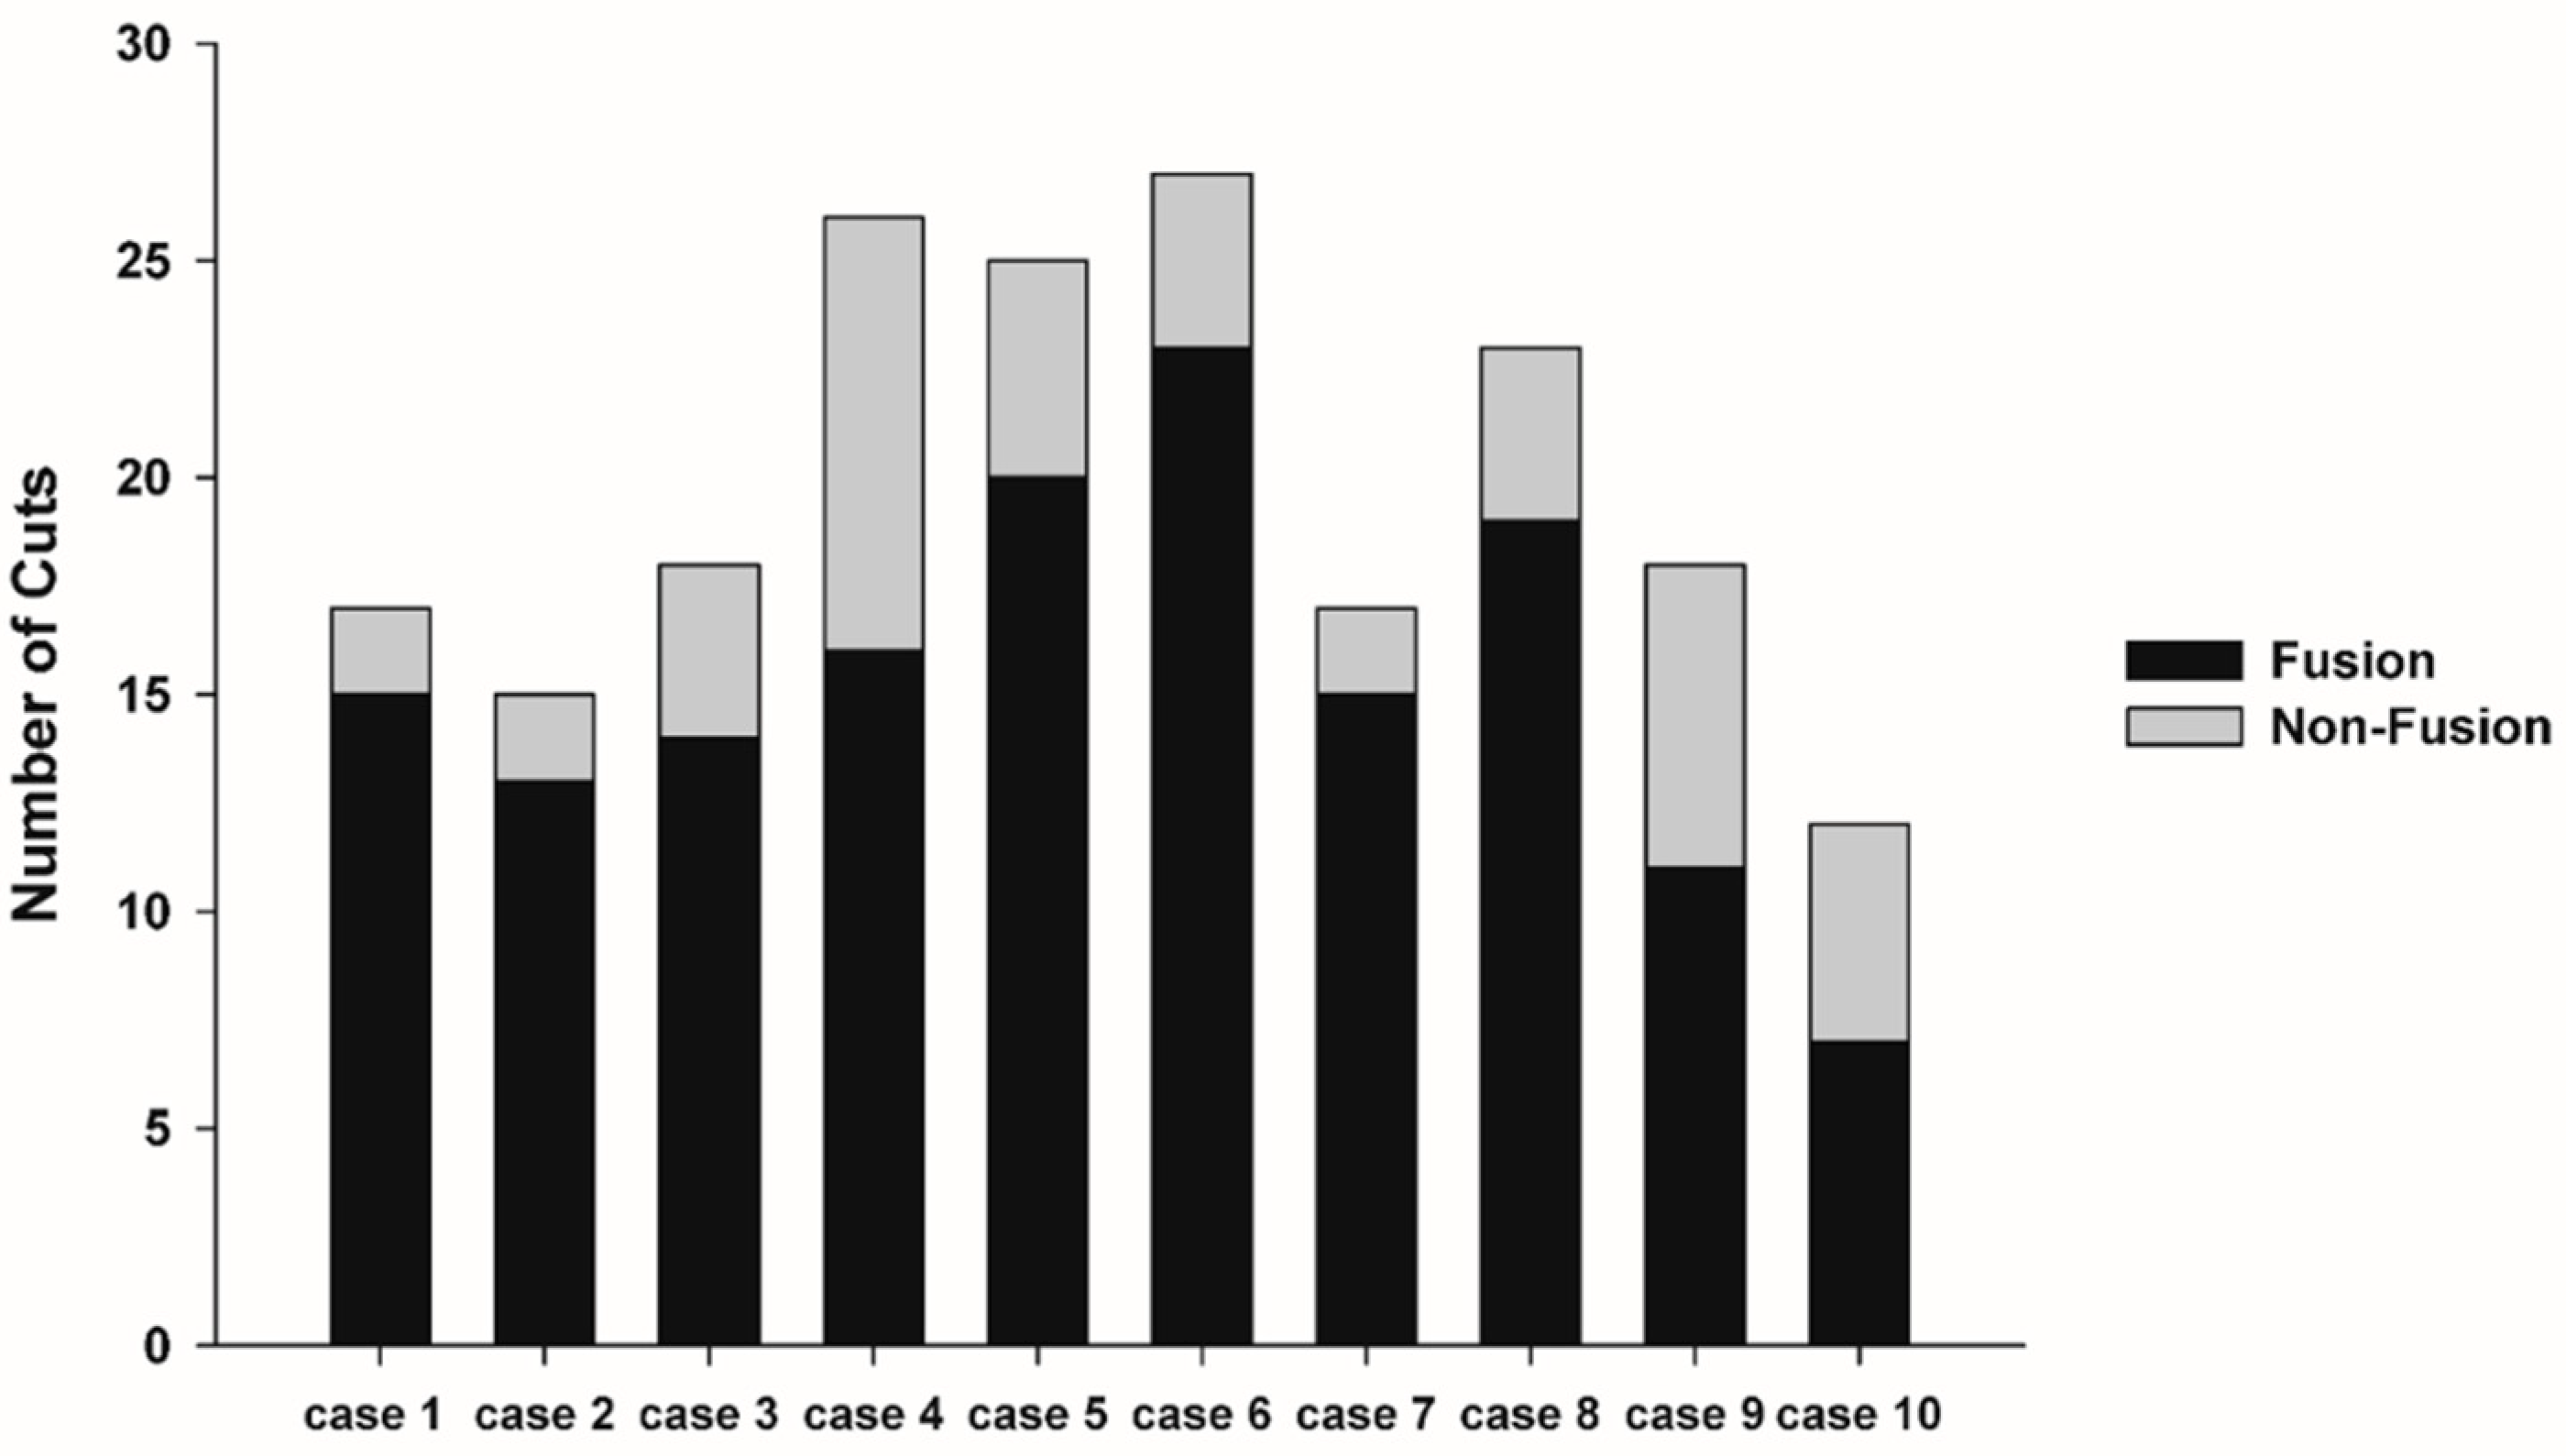

3.2. Fusion Rate Analysis Using 3D CT